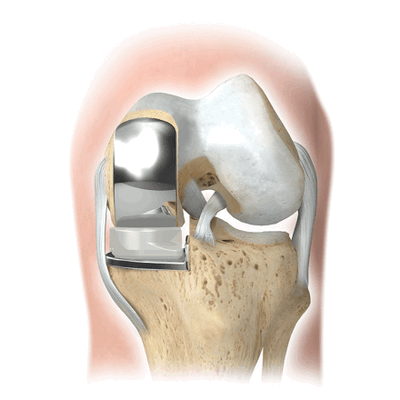

Если сустав поражен указанным на изображении образом, то возможна его частичная замена.

Основной метод лечения - постановка эндопротеза вместо поврежденного сустава. Раньше выполнялось преимущественно тотальное эндопротезирование коленного сустава, однако сейчас активно развивается другое направление - одномыщелковое (частичное) эндопротезирование.

Имплант на рентгене.